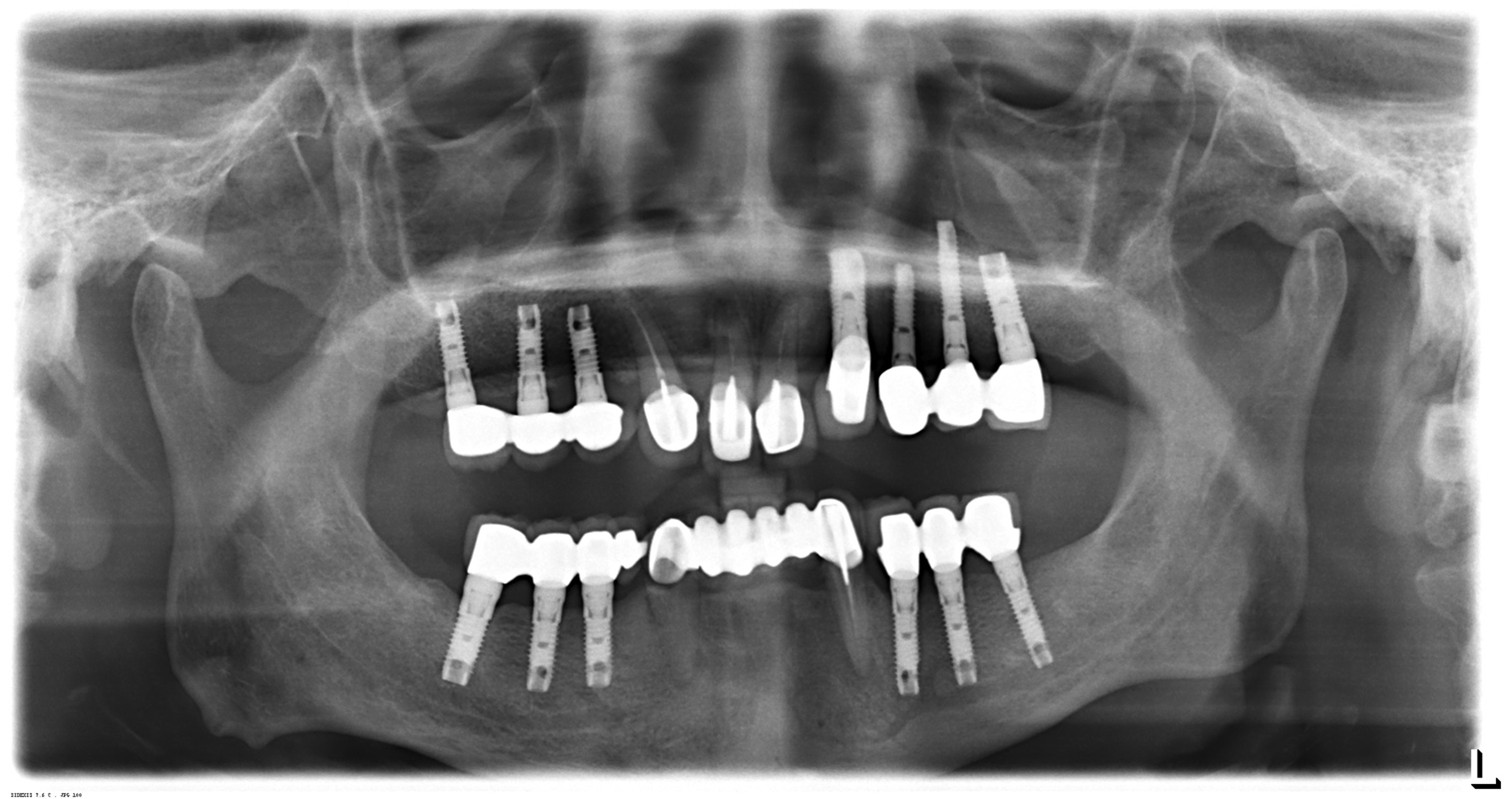

李先生長期配戴活動假牙,在日常咀嚼與使用上始終覺得不夠習慣。

初診時,李先生就很清楚地對宋醫師說:「我不追求快,只希望安全、可以用得久。」因此治療規劃並未急於進行,而是依照口腔條件、骨頭狀況與整體咬合,一步一步評估、逐步完成。

術後追蹤顯示:

對李先生而言,這次治療不是「一次完成」,而是選擇一條能陪自己走得長遠的方式。我們始終相信,治療的價值不在速度,而在於穩定、安心,與長期的使用品質。